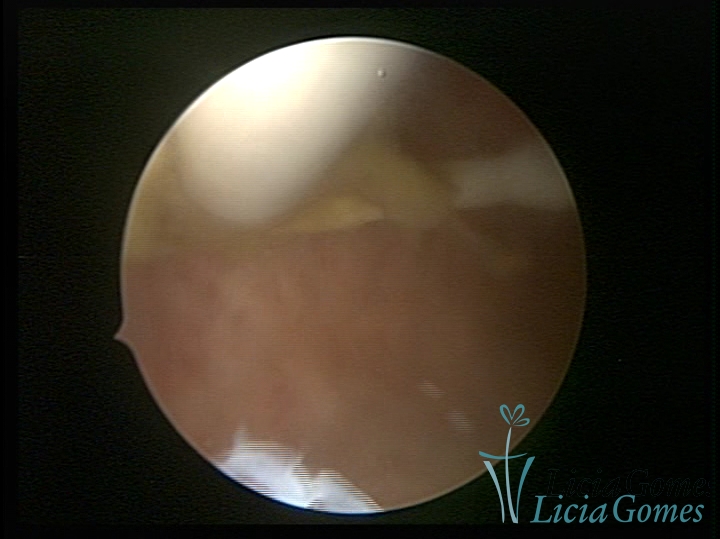

Canal cervical trófico, com o fio de Mirena®